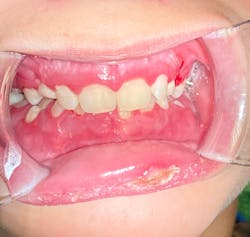

Note: The pictures are not of the highest quality as the patient was in extreme discomfort when I took them.

Differential considerations include:

Definitive diagnosis is likely one of two: Herpangina or acute primary herpetic gingivostomatitis

The saying “nothing is for certain unless it’s in a petri dish” stands true in all pathology cases, including this one. However, based on the symptoms and clinical presentation, I was able to surmise that it was more than likely either herpangina or APHG, although I’m leaning toward APHG.

For my patient, I prescribed Magic mouthwash, told him to rest (mom was on board with that), keep his oral cavity as clean as possible (several of my patients have found a diluted Listerine or chlorhexidine rinse to be helpful, but not all can tolerate it), and let it run its course. Mom was to contact me if it didn’t start to improve or get better after 10–14 days.